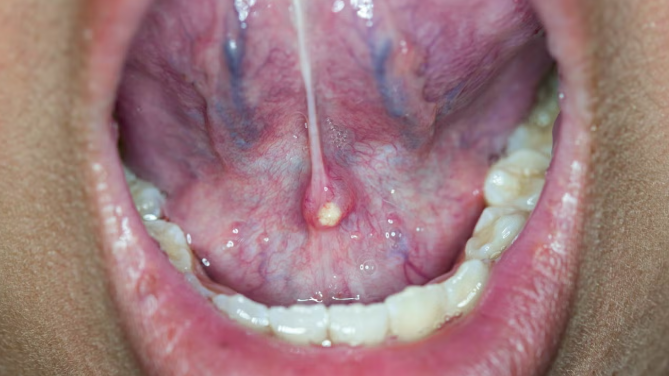

- 입안에서 고름이 나오거나 불쾌한 냄새/맛이 느껴짐

③ 타석증(침샘 결석)

침샘관 안에 돌(타석)이 생겨 침이 제대로 배출되지 않으면 반복적인 염증을 초래합니다. 타석 크기에 따라 저절로 배출되기도 하지만, 크거나 만성적인 경우 내시경적 제거 또는 수술이 필요할 수 있습니다.